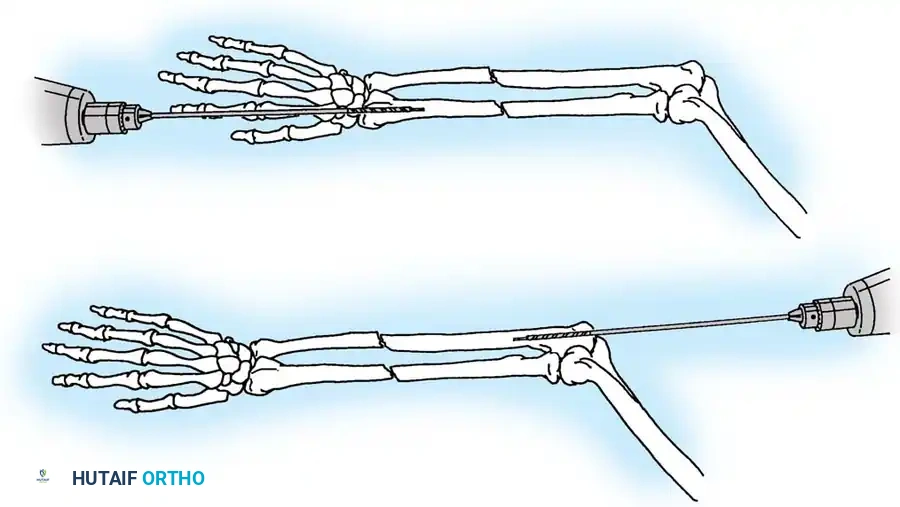

3. Excision of the Proximal Fragment

Excision is indicated primarily for elderly, low-demand patients with severe comminution where stable osteosynthesis is impossible, or when the articular surface cannot be congruously restored. Up to 50% of the olecranon can be excised without compromising elbow stability, provided the coronoid process and collateral ligaments remain intact.

🔪 Surgical Technique: Excision and Triceps Advancement

- Fragment Removal: Carefully dissect the comminuted fragments from the triceps tendon, preserving as much tendon length as possible.

- Joint Debridement: Inspect the joint and remove all intra-articular debris.

- Bone Preparation: Smooth the remaining proximal end of the ulna. If the midportion of the olecranon is comminuted but the proximal tip is intact, the central comminuted segment can be excised (Barford technique). The osteotomies must be directed accurately along the radius of the trochlear curve to reconstitute a smoothly curved notch.

- Triceps Advancement: Drill two or three longitudinal holes through the remaining proximal ulna. Pass heavy non-absorbable sutures (e.g., #2 or #5 FiberWire) through the triceps tendon using a Krackow stitch, pass them through the drill holes, and tie them securely over the posterior ulnar cortex with the elbow in 30 degrees of flexion.